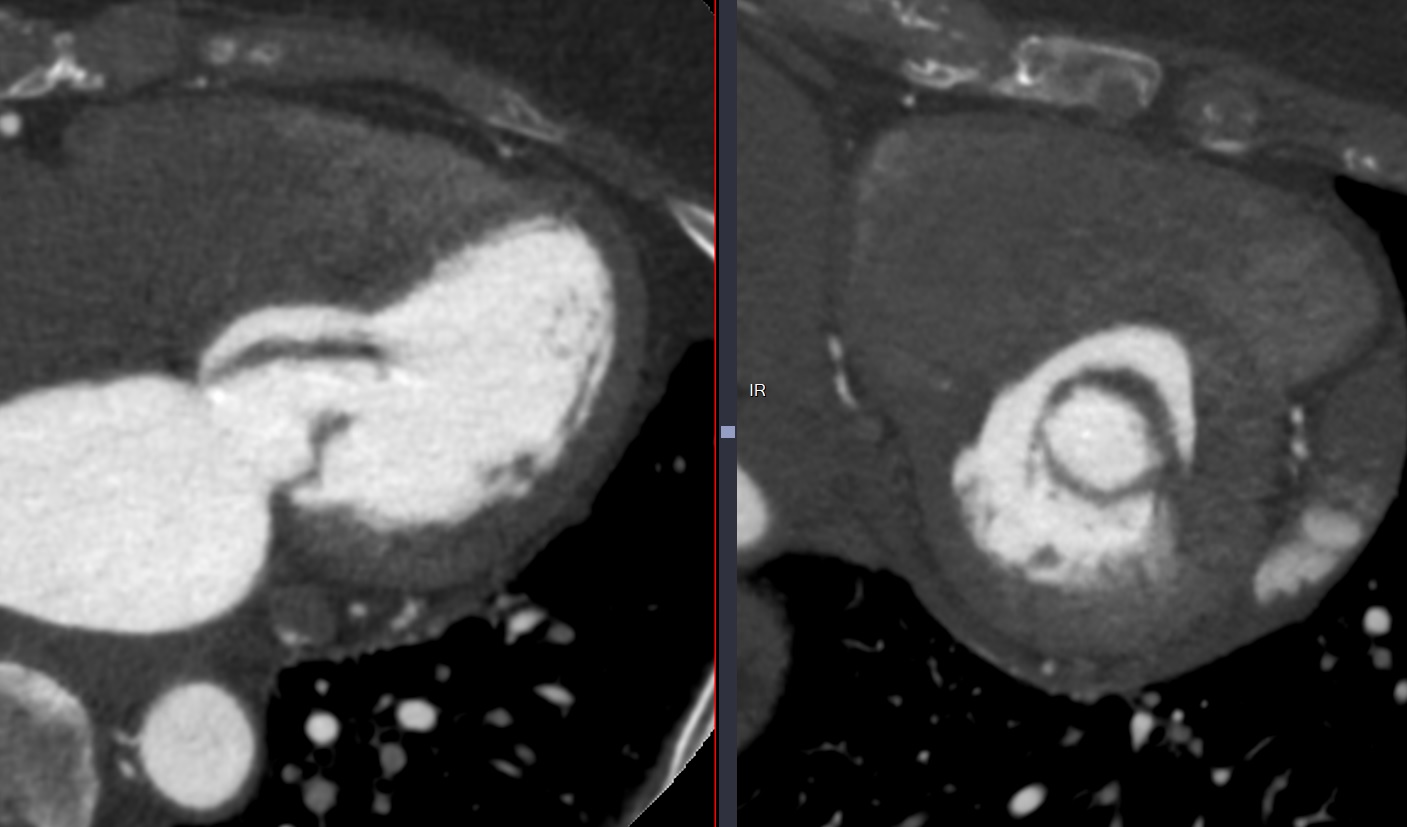

- Prolapsus mitral = Débordement (bowing) en systole de >2mm des feuillets dans l’OG

- Le prolapus est du a la rupture ou l’élongation des cordages

- Epaississement des feuillets (>5mm) fréquemment associée

Cas

Stenose Mitrale